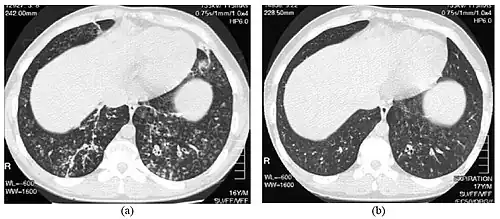

High-resolution computed tomography images of the lower chest in a 16-year-old boy with diffuse panbronchiolitis

Diagnosis

High resolution computed tomography (HRCT) images of the lower chest in a 16-year-old boy initially diagnosed with DPB (left), and 8 weeks later (right) after a 6-week course of treatment with erythromycin. The bilateral bronchiectasis and prominent centri-lobular nodules with a "tree-in-bud" pattern shows noticeable improvement.

The diagnosis of DPB requires analysis of the lungs and bronchiolar tissues, which can require a lung biopsy, or the more preferred high resolution computed tomography (HRCT) scan of the lungs.[7] The diagnostic criteria include severe inflammation in all layers of the respiratory bronchioles and lung tissue lesions that appear as nodules within the terminal and respiratory bronchioles in both lungs.[4] The nodules in DPB appear as opaque lumps when viewed on X-rays of the lung, and can cause airway obstruction, which is evaluated by a pulmonary function test, or PFT.[6] Lung X-rays can also reveal dilation of the bronchiolar passages, another sign of DPB. HRCT scans often show blockages of some bronchiolar passages with mucus, which is referred to as the "tree-in-bud" pattern.[7] Hypoxemia, another sign of breathing difficulty, is revealed by measuring the oxygen and carbon dioxide content of the blood, using a blood test called arterial blood gas. Other findings observed with DPB include the proliferation of lymphocytes (white blood cells that fight infection), neutrophils, and foamy histiocytes (tissue macrophages) in the lung lining. Bacteria such as H. influenzae and P. aeruginosa are also detectable, with the latter becoming more prominent as the disease progresses.[4][5] The white blood, bacterial and other cellular content of the blood can be measured by taking a complete blood count (CBC). Elevated levels of IgG and IgA (classes of immunoglobulins) may be seen, as well as the presence of rheumatoid factor (an indicator of autoimmunity). Hemagglutination, a clumping of red blood cells in response to the presence of antibodies in the blood, may also occur. Neutrophils, beta-defensins, leukotrienes, and chemokines can also be detected in bronchoalveolar lavage fluid injected then removed from the bronchiolar airways of individuals with DPB, for evaluation.[4][9]